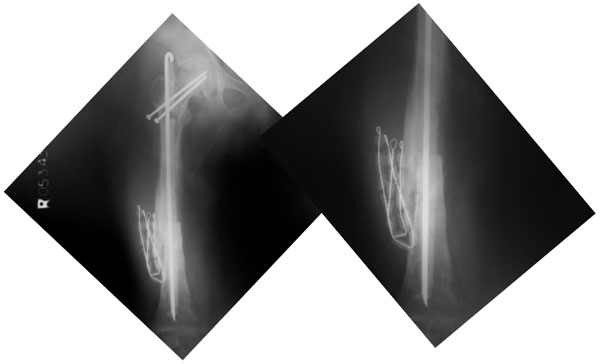

| The x-rays at 2 months after surgery show good progress of healing, resolution of the infection completely and improvement in the quality of the overall bone. The screws in the neck of the femur were applied because she developed a slipped capital femoral epiphysis (slippage of the growth plate of hip joint ball). |